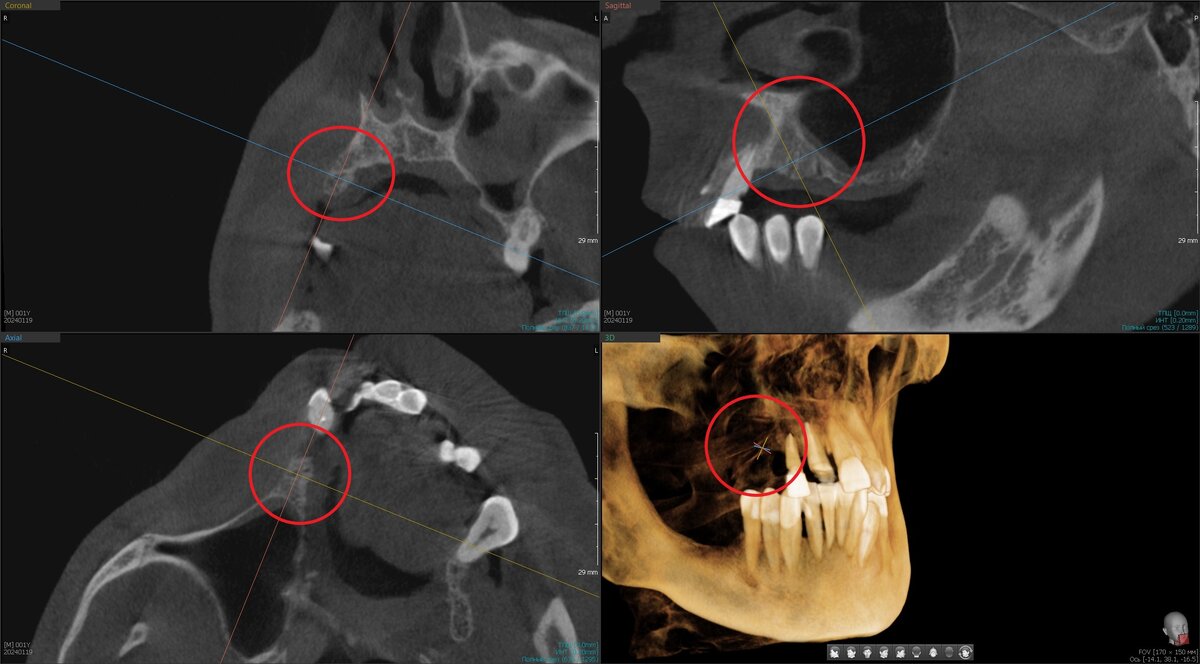

Загружаем туда данные КЛКТ (3Д КТ, рентген) и цифровой слепок челюстей (цифровой скан) - листайте, это просто примеры, не взаимосвязанные друг с другом:

Затем под это положение коронок расставляем имплантаты:

Расстановка имплантатов